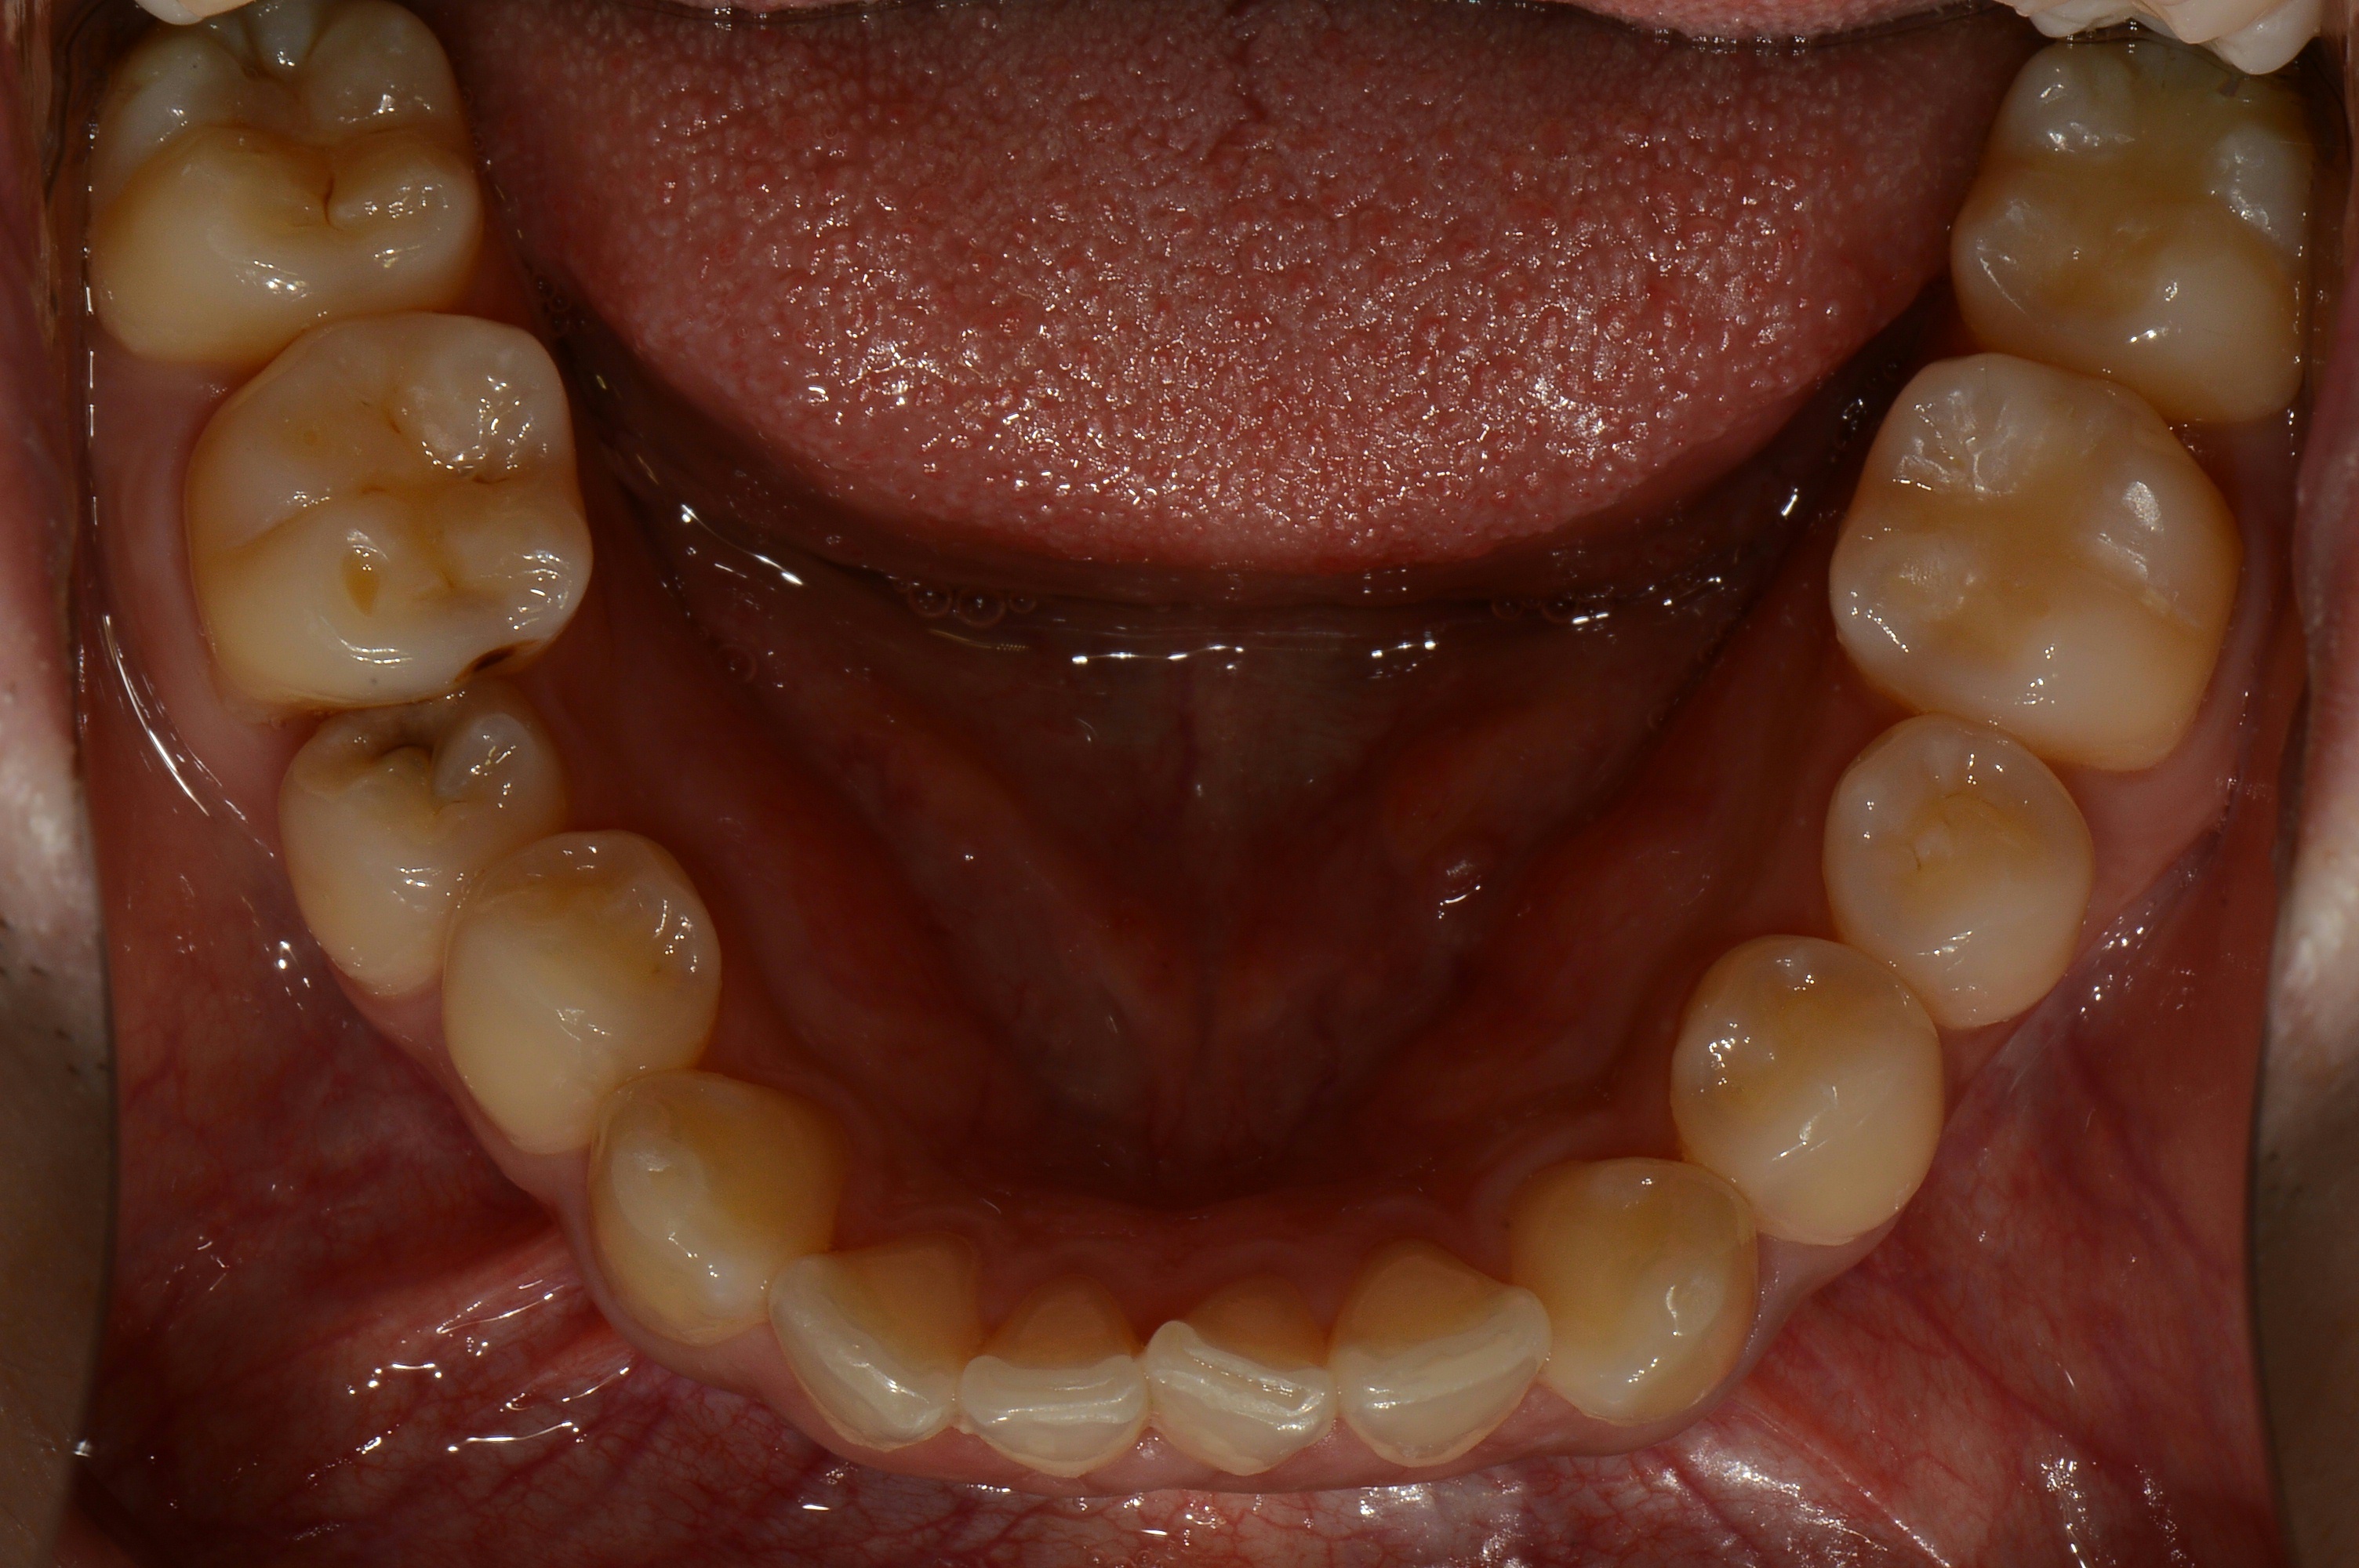

치료 전 사진입니다.